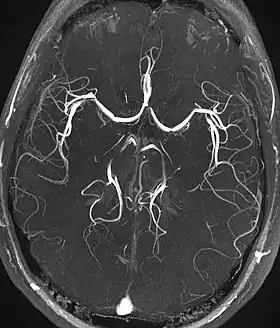

Magnetic resonance angiography (MRA) and venographyTime-of-flightTOFBlood entering the imaged area is not yet magnetically saturated, giving it a much higher signal when using short echo time and flow compensation. Detection of aneurysm, stenosis, or dissection[40]

Phase-contrast magnetic resonance imagingPC-MRATwo gradients with equal magnitude, but opposite direction, are used to encode a phase shift, which is proportional to the velocity of spins.[41] Detection of aneurysm, stenosis, or dissection (pictured).[40]

(VIPR)